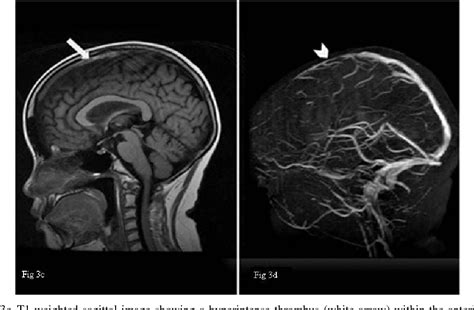

- Pe T1 nativ: hipofiza are semnal intermediar, iar „bright spot-ul” neurohipofizei (lobul posterior) se vede hiperintens.

- În adenom/hiperplazie: poate apărea o zonă izo- sau hipointensă pe T1.

- Pe T2: semnal variabil (uneori hiperintens în adenoame).

Imaginea de mai sus ilustrează un RMN sagital T1 al regiunii hipofizare, probabil evidențiind o glandă anormal mărită, prin disproporția vizuală în raport cu șaua turcească și conturul convex superior.

- Pe secvențele T1 precontrast, lobul posterior (“bright spot”) este hiperatenuat. În glandă mărită (hiperplazie sau adenom), acest semn poate fi modificat sau deplasat.

„Glanda hipofizară prezintă un volum crescut, cu contur superior convex și extindere supraselară ușoară. În secțiunile post-contrast, se observă captare neomogenă a gadoliniului, sugerând un proces intraglandular (posibil adenom macro). Posterior bright spot este prezent, dar ușor deviat superior.”